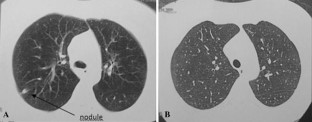

Changes in the spectrum of clinically important fungal infection have been observed in recent years. Acremonium species has been responsible for eumycotic mycetomas but has also been increasingly implicated in systemic fungal diseases. A case of Acremonium kiliense fungemia with proven involvement of the lungs in an allogeneic hematopoietic stem cell patient is reported. A high-resolution computed tomography scan of the lungs showed nodules in both lungs. Multiple cultures of blood demonstrated narrow septate hyphae, cylindrical conidia, and solitary tapering phialides and microconidia that remained grouped in slimy heads. The isolate was identified as A. kiliense based on its morphological characteristics and DNA sequence analysis. Susceptibility testing of the clinical isolate was performed to four antifungal agents. Amphotericin B, fluconazole and itraconazole were found to be inactive in vitro against the isolate; however, it was found to be sensitive to voriconazole. This last drug was indicated, and a high-resolution computed tomography scan of the lungs was normal after 10 days. One year later, the patient was free of symptoms and her blood culture was negative for fungi. Thus, voriconazole was effective in treatment for life-threatening A. kiliense infections. In this work, we performed an overview of worldwide clinical infections caused by A. kiliense.

Fig. 1

Fig. 2